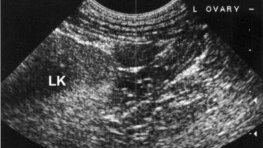

В ветеринарной практике мы нередко встречаем пациентов со вновь проявившимися признаками «течки» (эструса), через некоторое время после проведенной овариоэктомии (удаление яичников) или овариогистеректомии (удаление яичников и матки). Данное осложнение носит название овариореминантный синдром или реминант яичников – наличие функциональной ткани яичника. Причин может быть несколько, а именно: - неполное удаление тканей яичников; - реваскуляризация (восстановление кровоснабжения) тканей яичников, случайно оставленных/уроненных в брюшной(ую) полости(ь)...